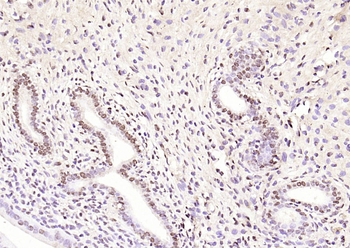

Phospho-CDKN1A/p21 (Thr145) Rabbit Polyclonal Antibody [orb6568]

FC, IF, IHC-Fr, IHC-P

Mouse, Rat

Human, Mouse, Rat

Rabbit

Polyclonal

Unconjugated

100 μl, 50 μl, 200 μlPhospho-CDKN1A/p21 (Ser130) Rabbit Polyclonal Antibody [orb6571]